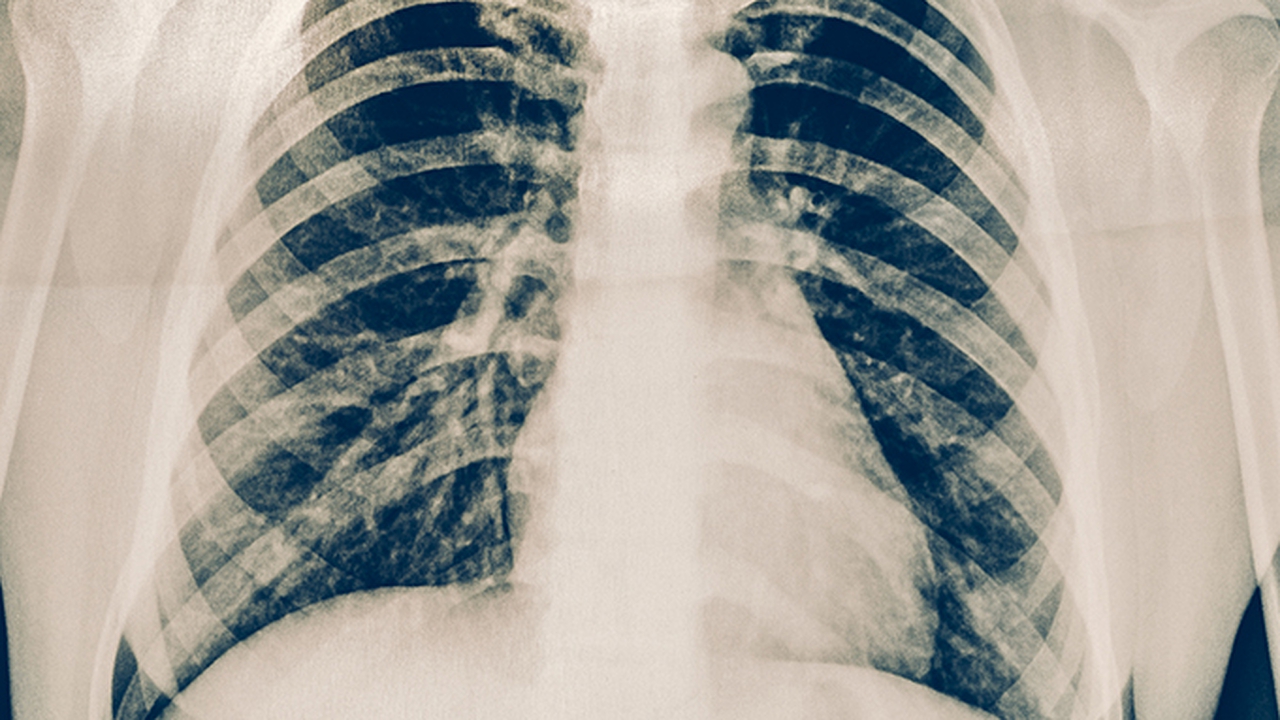

济南哪个医院治疗肺癌专业

济南治疗肺癌比较专业的医院有山东省肿瘤医院、山东大学齐鲁医院、山东省立医院、济南市中心医院、山东第一医科大学第一附属医院。这些医院在肺癌的诊断、治疗和科研方面具有丰富的经验,能够为患者提供全面的医疗服务。其中,山东省肿瘤医院、山东大学齐鲁医院和山东省立医院在肺癌治疗领域尤为突出。